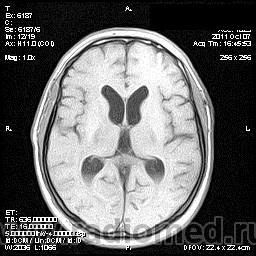

на МРТ - Определяется скопление крови в препонтинной цистерне, в проекции супраселлярной цистерны, в кортикальных бороздах полушарий головного мозга,  в проекции краниоспинального перехода. Выявляется горизонтальный уровень крови в задних рогах боковых желудочков. Боковые, третий желудочки резко расширены. Определяется перивентрикулярное повышение интенсивности сигнала от белого вещества головного мозга. Срединные структуры не смещены. Кортикальные борозды умеренно сглажены. Сильвиев водопровод прослеживается на всем протяжении. Отмечается смещение дна третьего желудочка каудально, с резким уменьшением размеров супраселлярной цистерны; базальные цистерны уменьшены в размере.

В проекции базальной артерии определяется аневризма размером до 4х6 мм.